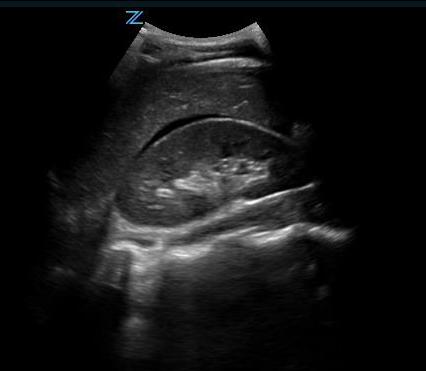

- This gives a coronal view of the interface between the liver and kidney. (Fig. 5) It is important to follow the lower edge of the liver caudally until a good view of the liver tip is obtained as fluid will often collect there first. (Video 4)

- Free fluid is usually seen in Morison’s pouch or along the lower edge of the liver and around the lower tip of the liver. (Figure 5, Videos 5-8)

- Figure 5. Small amount of free fluid Morison’s pouch view